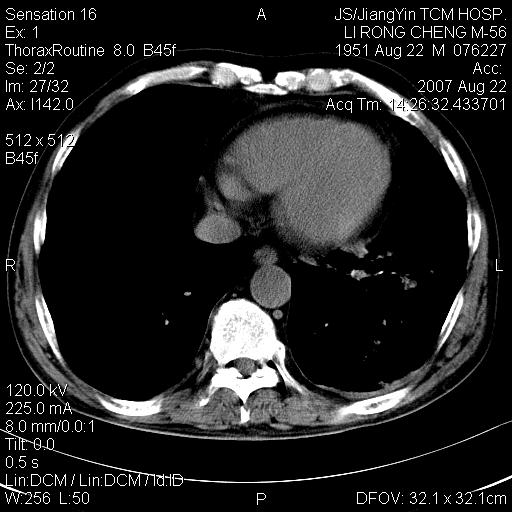

标题: CT9479:M,56Y,DM病史,咳嗽发热5天.肺脓疡.肺癌? [打印本页]

标题: CT9479:M,56Y,DM病史,咳嗽发热5天.肺脓疡.肺癌?

边灶边缘较光整,冠状位病灶呈大片状,,内有空洞,有胸膜反应,但无明显胸膜外侵犯征像,结合病史支持考虑肺肿脓,不排除结核,治疗后复查

好多钙化灶哦,病灶位于下叶背段,或许考虑结核更合适,做下相应检查先

左肺下叶见类软组织密度影,其内密度不均,有小空洞,广基与胸膜相连,其周见斑片状致密影.

考虑肺肿脓,不排除结核.

左肺下叶支气管呈小囊状扩张。下叶背段有类圆形高密度影,边缘模糊,外与胸膜相连。左侧胸膜增厚粘连。心包膜增厚。结合病史考虑1支扩并感染2胸膜及心包炎。

左下肺团片状类软组织密度影,形态不规则,边缘欠规整,其内可见液化区及气体影,病灶内侧见引流支气管影,相邻胸膜反应性增厚。病灶周围肺野内见增粗支气管,壁厚,边缘模糊。考虑:支气管扩张并感染;肺脓肿。

支持肺脓肿,左下叶见广泛浸润,并见支扩改变。建议治疗后复查。

考虑左下肺感染,脓肿形成,左下肺支气管扩张,左侧胸膜增厚。其他待排,治疗复查